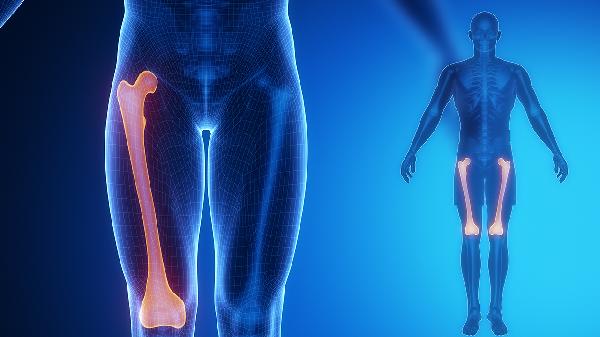

多数软骨瘤患者早期无明显疼痛,随着肿瘤增大可能出现间歇性隐痛,活动后加重。疼痛可能与肿瘤压迫周围神经或骨膜牵张有关。若突发剧烈疼痛伴肿胀,需警惕病理性骨折可能。长骨软骨瘤疼痛症状较手部肿瘤更为显著,可能与负重受力有关。

3、病理性骨折

当肿瘤导致骨质严重破坏时,轻微外力即可引发病理性骨折,表现为突发剧痛、功能障碍和畸形。骨折好发于长骨及负重部位,X线可见骨折线穿过溶骨病灶。儿童患者骨折后可能出现异常骨痂形成,需与恶性变鉴别。